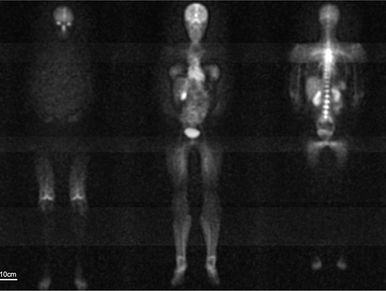

Sodium-23 ions play a vital physiological role in tissue and promise to provide markers for tissue viability as well as for kidney function and other clinically useful parameters. However, signal for sodium MRI is ~20 000 times lower than for normally used hydrogen-1 based MRI. We explore circuits and methods to boost signal-to-noise ratio for sodium MRI.

The image shows Sodium Magnetic Resonance Images of a female volunteer at 3T (6mm x 6mm in-plane resolution, 72mm slice thickness, captured in 50minutes for five segments) [Wetterling, Friedrich; Corteville, Dominique; Kalayciyan, Raffi; Rennings, Andre; Konstandin, Simon; Nagel, Armin; Stark, Helmut; Schad, Lothar (2012-06-22). "Whole body sodium MRI at 3T using an asymmetric birdcage resonator and short echo time sequence: first images of a male volunteer". Physics in medicine and biology. 57 (14): 4555–4567. doi:10.1088/0031-9155/57/14/4555. PMID 22722731.]